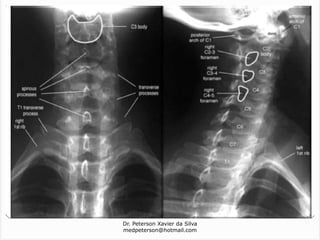

Região cervical (CI – CVII)

Os processos espinhosos de C1-6 freqüentemente são bífidos;

Todas as vértebras cervicais possuem três forames: um forame

vertebral e dois forames transversários